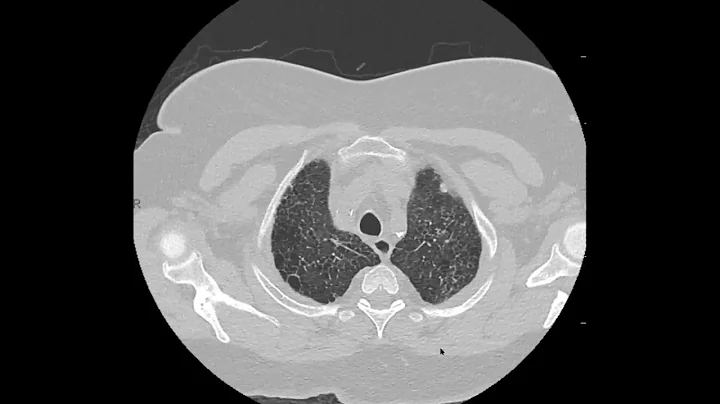

Pulmonary Langerhans Cell Histiocytosis (plch) On Ct

Nice example of how earlier on in disease, it is easier to make a confident diagnosis in ILD cases. Also, classic appearnce of ...